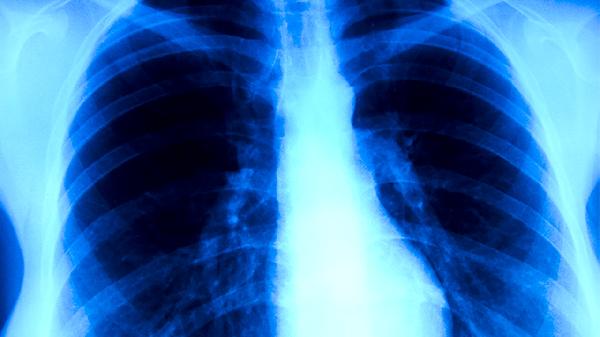

慢性阻塞性肺病会引起肺结核吗 慢性阻塞性肺病引发的并发症细说

慢性阻塞性肺病一般不会直接引起肺结核,但可能增加肺结核的发病概率。慢性阻塞性肺病可能引发肺源性心脏病、自发性气胸、呼吸衰竭、肺部感染、骨质疏松等并发症。